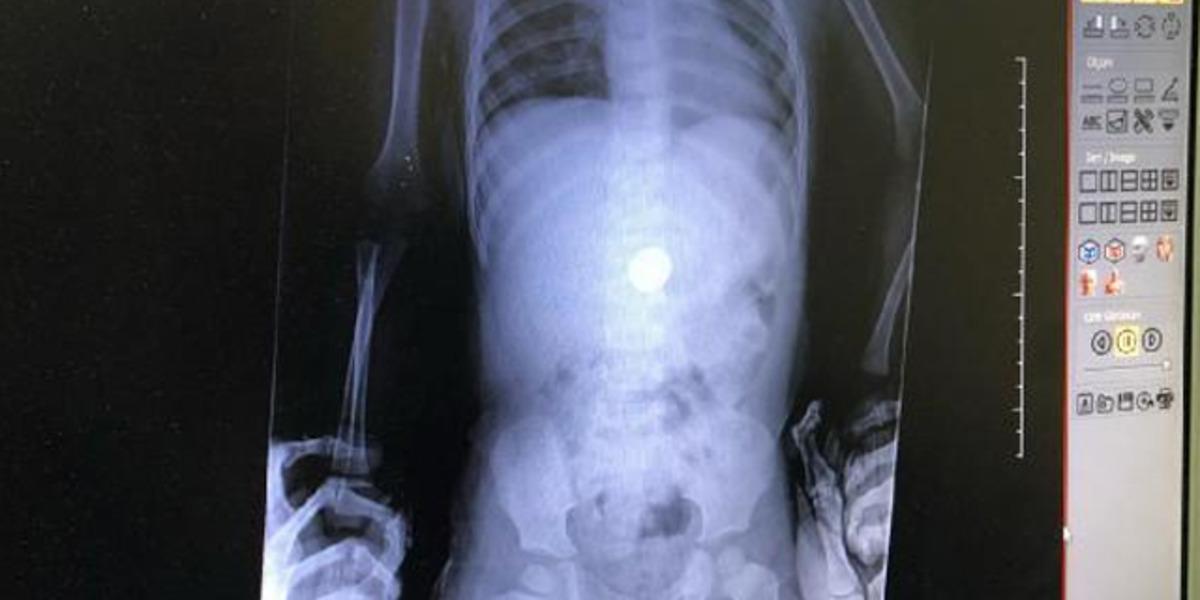

Zonguldak Kadın Doğum Çocuk Hastalıkları Hastanesi'ne 16 Ocak'ta başvuran aile, doktorlara çocuklarının madeni para yuttuğunu söyledi. Dr. Sertaç Akman, çekilen röntgende E.İ. isimli erkek çocuğun midesindeki 25 kuruşluk madeni parayı tespit etti. E.İ.'nin yapılan muayenesinde madeni paranın yemek borusuna zarar vermediği anlaşıldı. Doktorlar, gerekli tetkikleri yaptıktan sonra E.İ.'nin parayı doğal yollarla çıkarması için taburcu edip evine gönderdi. Takibe alınan E.İ.'nin normal yolla parayı çıkaramaması halinde endoskopi veya ameliyat gibi farklı yöntemlerle paranın çıkarılabileceği öğrenildi.